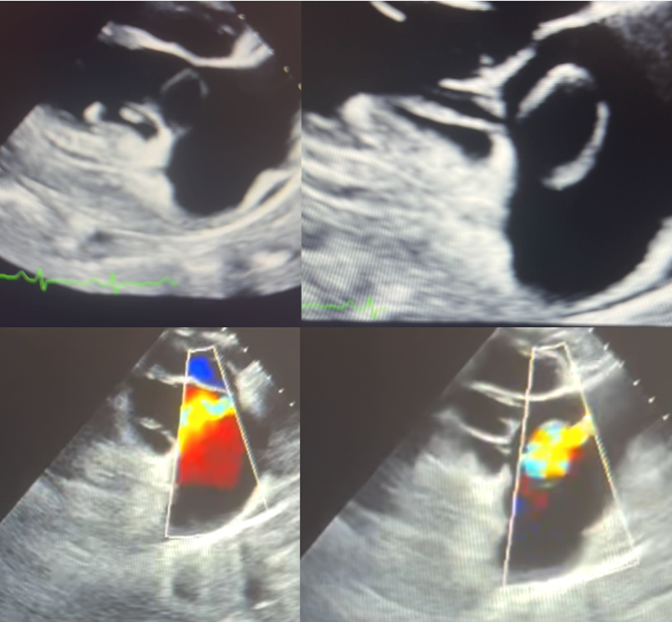

Transthoracic echocardiography demonstrated a moderately reduced left ventricular ejection fraction (EF 40–45%), a mobile structure adjacent to the tricuspid valve, severe tricuspid regurgitation, and dilation of the right-sided heart chambers. Coronary angiography revealed normal coronary anatomy and no significant coronary artery disease. Transesophageal echocardiography further identified a sinus of Valsalva aneurysm involving the noncoronary cusp. A cardiac magnetic resonance imaging (CMR) study was subsequently ordered to further evaluate cardiac structure and function.

Figure 2: Transesophageal echocardiographic evaluation of the tricuspid valve. The left panes depict diastole, and the right panes depict systole; corresponding color Doppler imaging is shown in the lower panels. A cystic-appearing structure adjacent to the tricuspid valve annulus is noted, with color flow observed during both systole and diastole—findings suggestive of an aorto-atrial shunt from a ruptured sinus of Valsalva aneurysm.